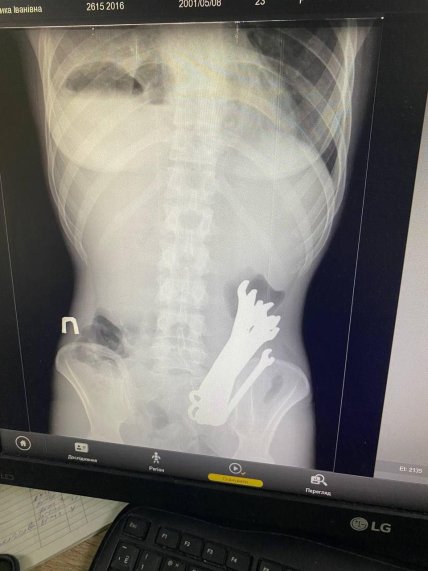

Рентген-снимок пациента до операции

В Черкассах врачи извлекли из организма пациента шесть гаечных ключей, которые он проглотил. Инцидент произошел в августе, когда рентген обнаружил инородные тела в организме больного.

"Пациент госпитализирован в стационар с флегмоной шеи (гнойное воспаление мягких тканей. – Ред.), разрывом пищевода на уровне глотки и средней трети, тотальным медиастинитом (воспаление средостения. – Ред.), эмпиемой плевры с правой стороны (скопление гноя. — Ред.), инородными телами и опущением желудка", — говорится в сообщении отделения хирургии.